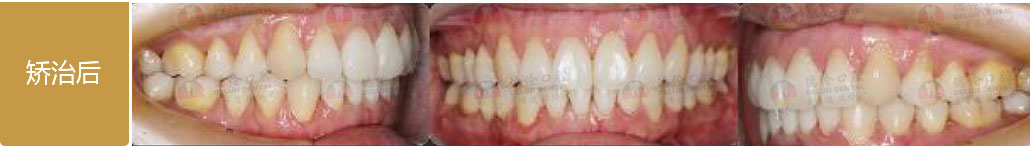

矯治采用兩種不同的厚度的膜片(牙套),發揮兩種不同膜片的各自優勢,在有效的作用時間內,矯治效率、矯治目標達成和舒適度方面較普通隱形矯正方式有明顯提升。

厚薄兩種矯治器,每周替換有利于牙齒位置的準確控制